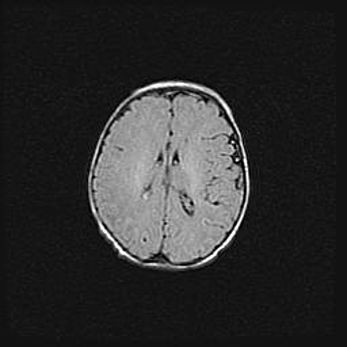

Множественные кисты обоих полушарий головного мозга, наибольшая из них в правой затылочной области. Ассиметричная атрофическая гидроцефалия.

Возраст: 7 месяцев

Вес: 5660 г

Пол: мужской

Окружность головы: 41,5 см

Срок гестации: 28-29 недель

Кисты головного мозга развиваются в результате многоочаговых некрозов вещества мозга и возникают вследствие перенесенной перинатальной инфекции, менингитов, энцефалитов, асфиксии, родовой травмы, расстройств мозгового кровообращения различного генеза. Образованию кист в веществе головного мозга плодов и новорожденных способствуют такие факторы, как высокое содержание в нем воды, недостаточная (или отсутствие) миелинизация и слабая астроглиальная реакция на повреждение.

Кисты могут сочетаться с гидроцефалией и другими поражениями головного мозга.